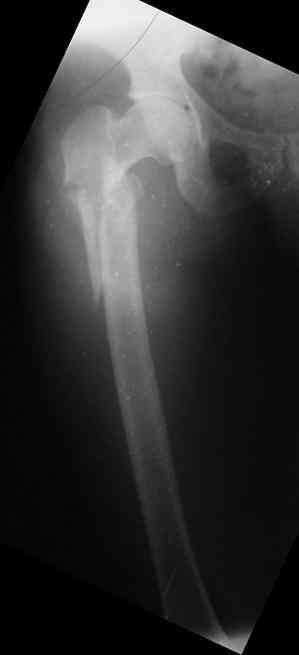

Male, 75 yrs old.

Right hip fracture as an interthrocanteric with extension to diaphysis Tronzo V.

Option for treatment:

1. DHS

2. 90 - 95 g AO Plate (Condylar Plate)_

3. Reconstruction Hip Nail

4. Intertrochanteric Nail System

5. Externa hip fixator

6. None of the above.